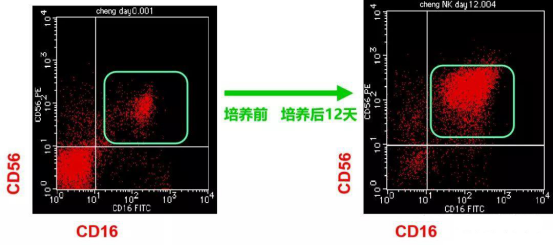

随后的8个月里,患者接受了一系列的手术、化疗和药物治疗。2017年3月,他开始尝试NK细胞输注治疗,值得一提的是,患者在NK细胞治疗期间,除营养支持、心理干预等辅助疗法之外,未接受其他治疗。

数量补充:通过体外培养,NK细胞数量可扩增数百倍,解决“兵力不足”的问题

质量提升:特殊细胞因子激活使细胞恢复到最有战斗力的状态